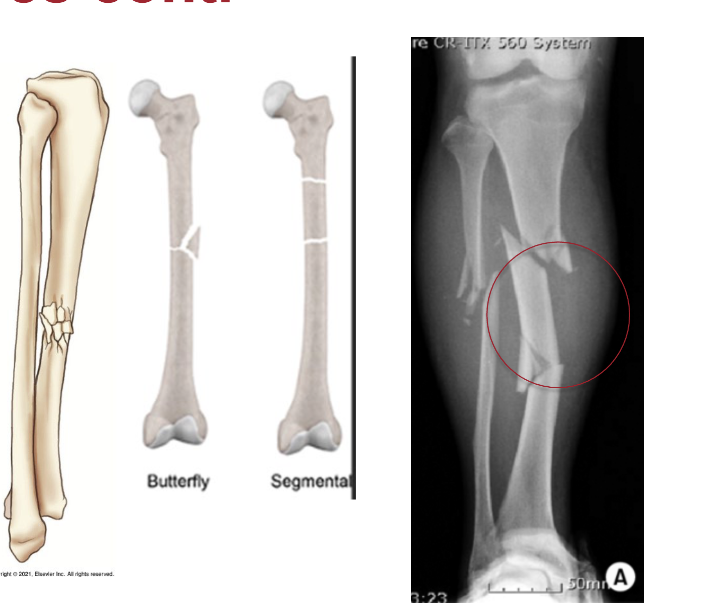

What is a comminuted fracture?

Bone is splintered or crushed at site of impact resulting in two or more fragments

Segmental

Butterfly

What type of fracture is this?

Butterfly -comminuted

Segmental - comminuted